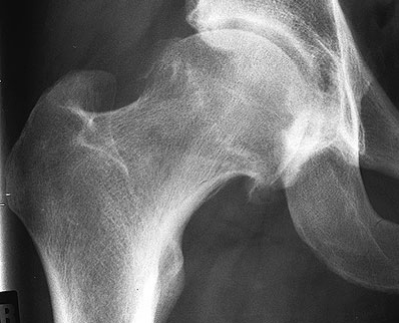

Während der Ruhehaltung kann es aber dazu kommen dass die Schmerzen als intensiver wahrgenommen werden. Die Hüfte ist das Gelenk an dem sich das Acetabulum des Beckenknochens und der Femurkopf treffen. Hüftmuskelschmerzen kann man im ganzen Hüftgebiet haben.

Jugend erworbene Formstörungen des Hüftgelenkes. Hüftmuskel-Schmerzen werden häufig als dumpf bohrend beschrieben. Die meisten Menschen beziehen sich auf die Beckenknochen als Hüfte genauer gesagt auf den obersten Teil der als Ilium bekannt ist.

In einer Studie aus dem Jahr 2018 über muskuloskelettale Probleme in der Schwangerschaft 321 der 184 Teilnehmer gaben an während der. Dazu gehören insbesondere die Hüftdysplasie angeborene Steilstellung des Hüftdaches und das Impingement Einklemmung zwischen Hüftkopf und Pfanne. Hüftschmerzen sind wie alle Schmerzen eine lästige Angelegenheit und können zu Bewegungseinschränkungen jeglicher Art führen.

Die Hüfte ist das Gelenk an dem sich das Acetabulum des Beckenknochens und der Femurkopf treffen.

Bei vielen Menschen wird diese Gleit- und Pufferschicht im Gelenk so weit zerstört dass schließlich Knochen auf Knochen trifft. Aber auch eine Knochenmarksentzündung Osteomyelitis kann durch Fortleitung der Bakterien zu einer Hüftentzündung führen. Mit zunehmendem Alter nutzt sich der gesunde Gelenkknorpel ab. Dazu gehören insbesondere die Hüftdysplasie angeborene Steilstellung des Hüftdaches und das Impingement Einklemmung zwischen Hüftkopf und Pfanne. Sie können entweder vom Muskel oder einem gereizten Nerv herrühren. Der Teil der leicht zu fühlen ist ist der Beckenkamm. Schmerzen in der rechten Hüfte kann in zwei Stellen des Körpers auftreten. Organe die über der rechten Hüfte liegen. Die Schmerzen in der Hüfte oder beim Liegen können nicht immer simpel zugeordnet werden.